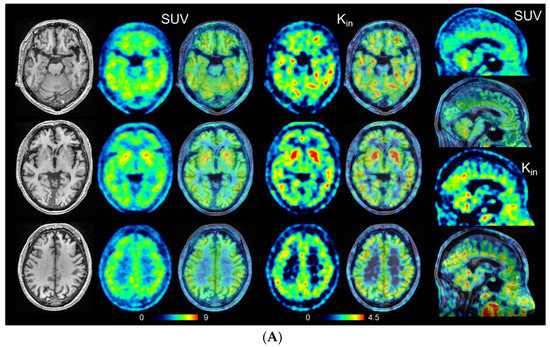

There were no significant differences in the distributions of age, disease duration, and education between patients with eAD and the HCs. The mean MMSE score was significantly lower in the eAD group (23.7 ± 2.6) than in the HC group (29.2 ± 0.9, p < 0.0001) (Table 1). The mean CDR and CDR sum of boxes (CDR-SB) scores were significantly greater in eAD patients than in HCs (p < 0.0001 for both). As confirmed by the 11C-PiB PET images, all patients were found to have positive cortical accumulation of PiB and all HC subjects had negative accumulation. SUV and Kin images of representative cases are presented in Figure 3. The distribution of both parametric values was similar, with cortical accumulation tending to be higher in eAD than in HCs, especially in the PCC and hippocampus.

Figure 3.

Representative images of HCs (A) and eAD (B) for SUV and Kin (mL/min/100 g) PET image (left) and fusion image (right). The right end column shows sagittal view of SUV (top two rows) and Kin (bottom two rows). The left end column shows T1WI-MRI of identical slice location. Note accumulations of the PCC and hippocampus are elevated in eAD patients compared with HCs.